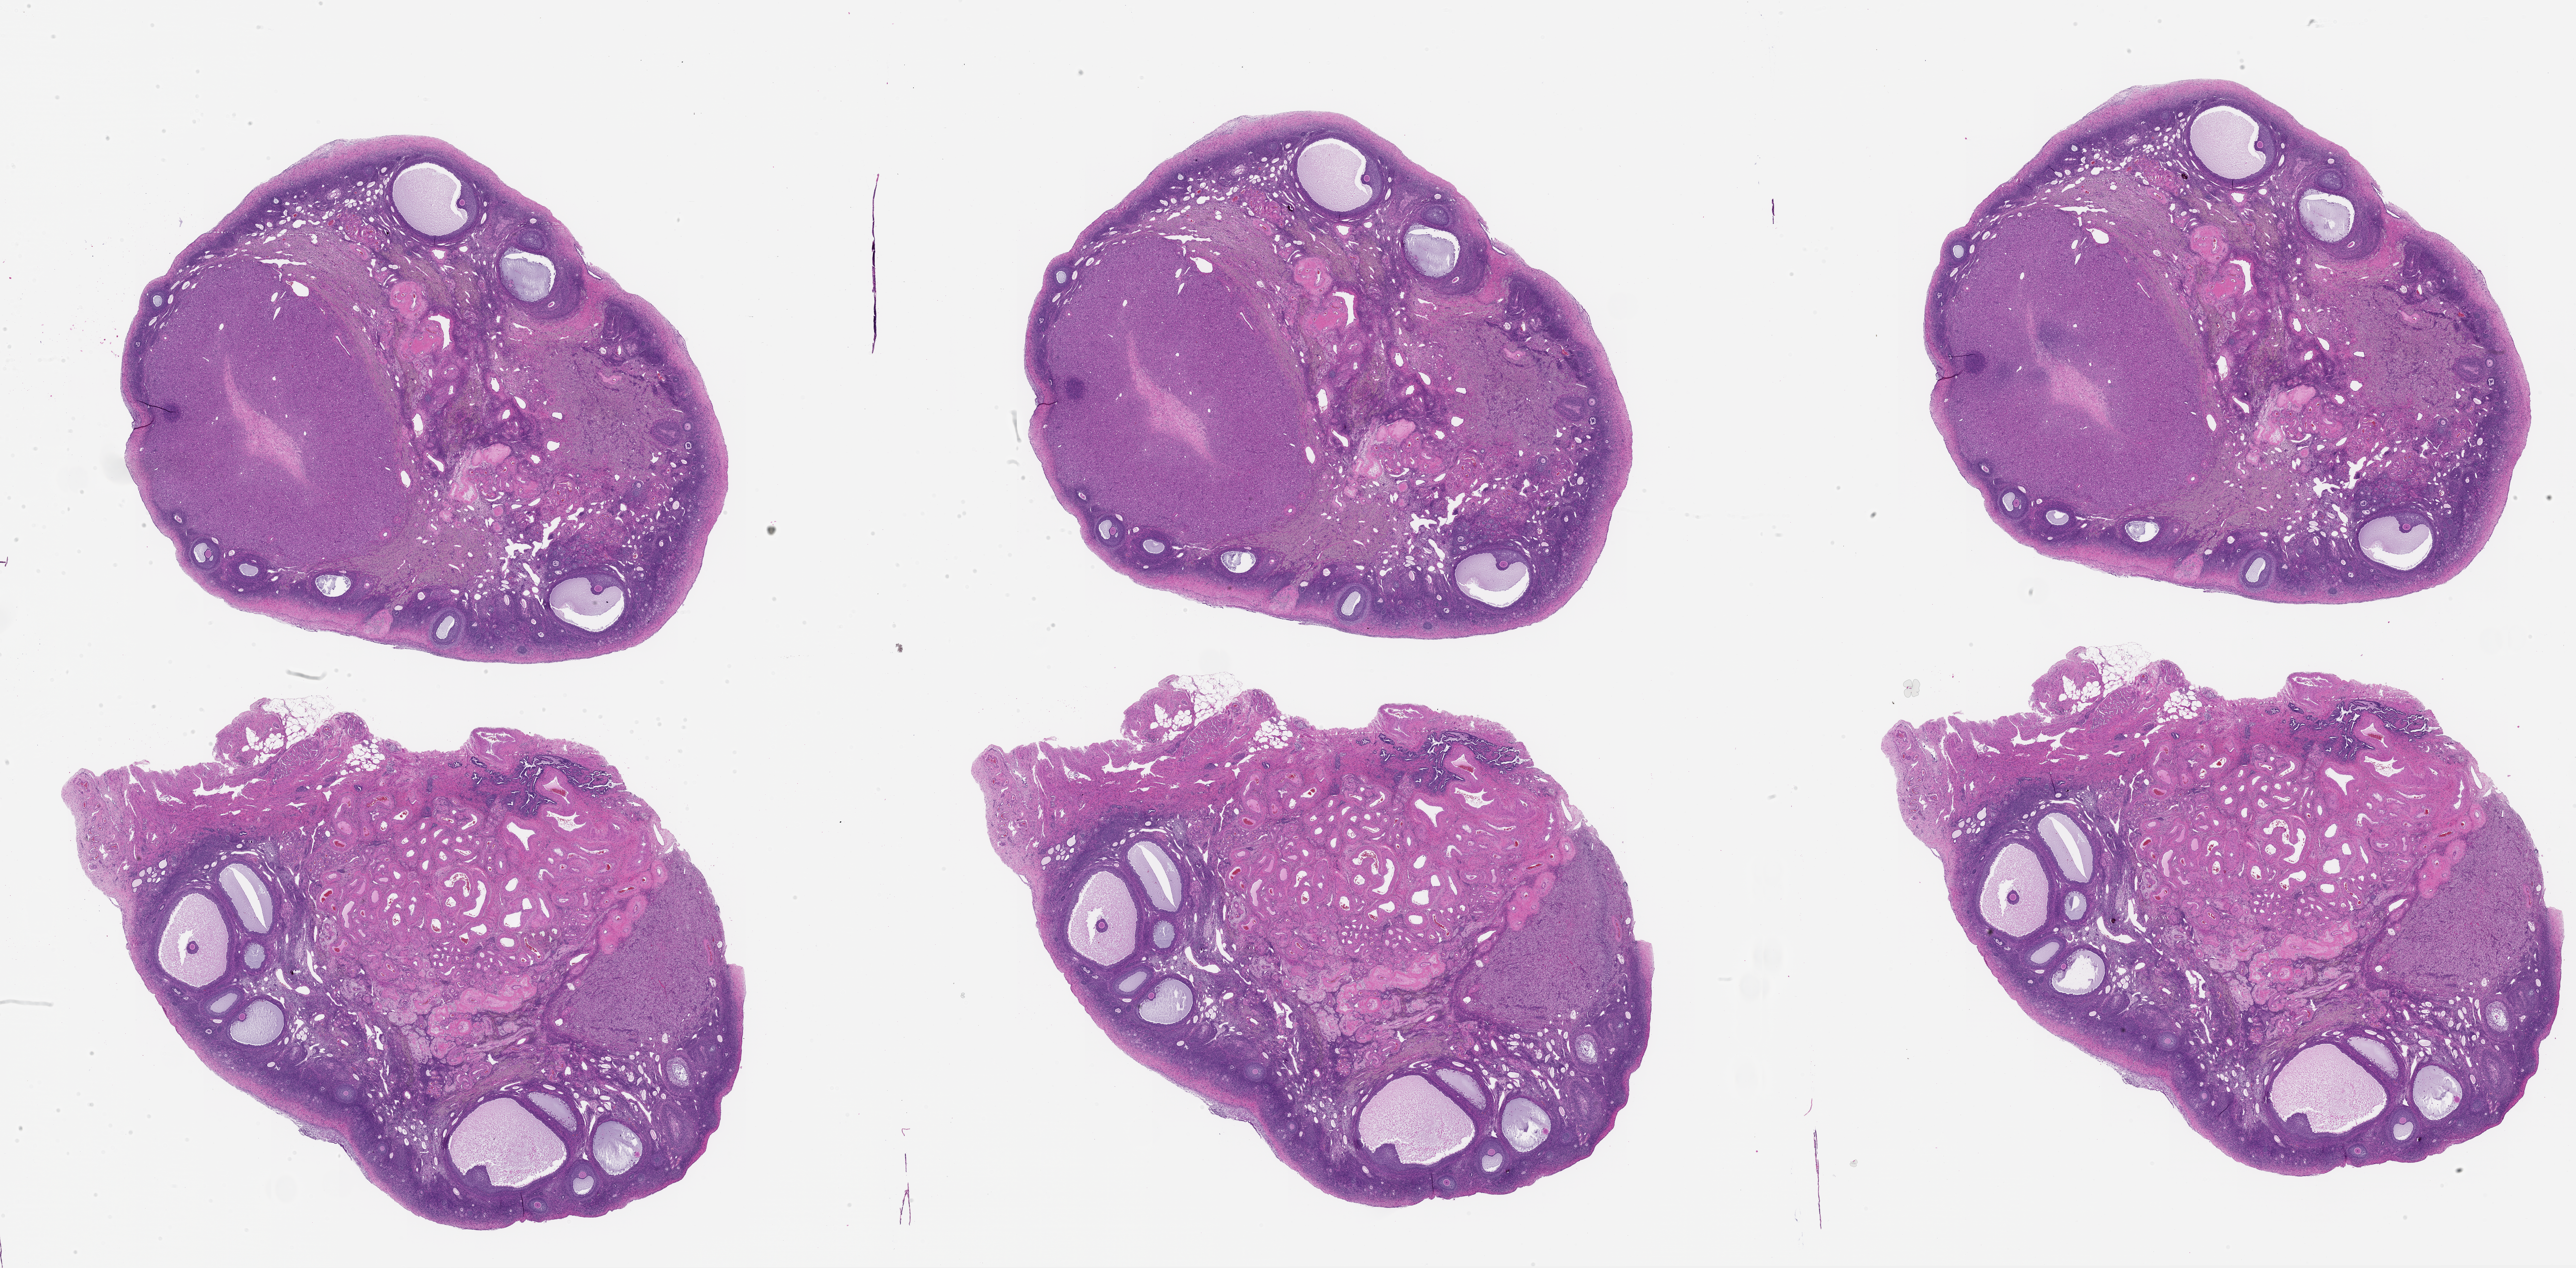

M. Zelinski, 2026, 'Zelinski Lab: Papio hamadryas Donor MZ_PH_39220 Ovary Left Slide 60', https://mother-db.org/MDB0000625, Multispecies Ovary Tissue Histology Electronic Repository, Retrieved: April 17, 2026

Genus: Papio (baboons)

Species: Papio hamadryas (hamadryas baboon)

Donor ID: MZ_PH_39220

Life Stage: aging

Age: 18 years, days

Stage of Cycle: luteal

Accession #: MDB0000625

Ovary position: left

Location: wholeOvary

Section thickness: 5 microns

Fixation: paraformaldehyde4

Stain: hematoxylinAndEosin